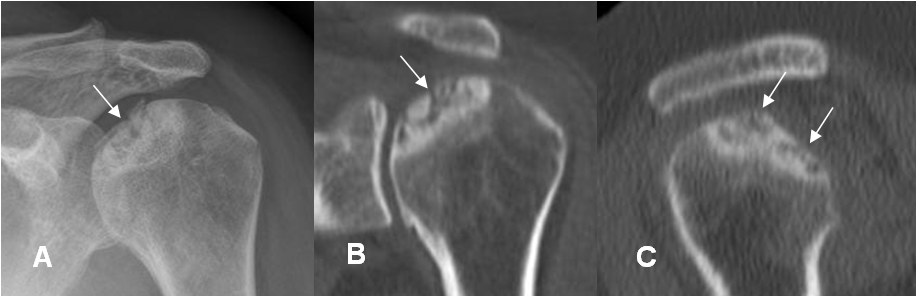

Fig 161 B. Artropatía degenerativa.

A: Rx AP, B: TAC reconstrucción coronal y C: TAC reconstrucción sagital. Cambios degenerativos en la cabeza humeral, con formación de lesiones osteocondrales.